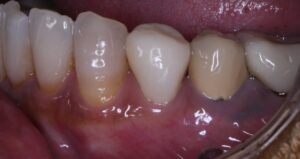

この患者様は「側切歯が先天性に欠損しおり、犬歯の尖りを直したい。」と来院されました。歯の色も白くしたいと希望がありましたので、ホワイトニングにより色調を改善した後に修復することになりました。

本来、側切歯があるところに犬歯がきているため、何か違和感がある印象を受けます。それではどの様にこの歯の形態を修復すれば良いでしょうか。

治療前後に顔貌写真と口腔内写真です。患者さんには大変満足していただけました。破折や変色のリスクがありますが、費用対効果が高く審美的に大変満足いく結果となりました。